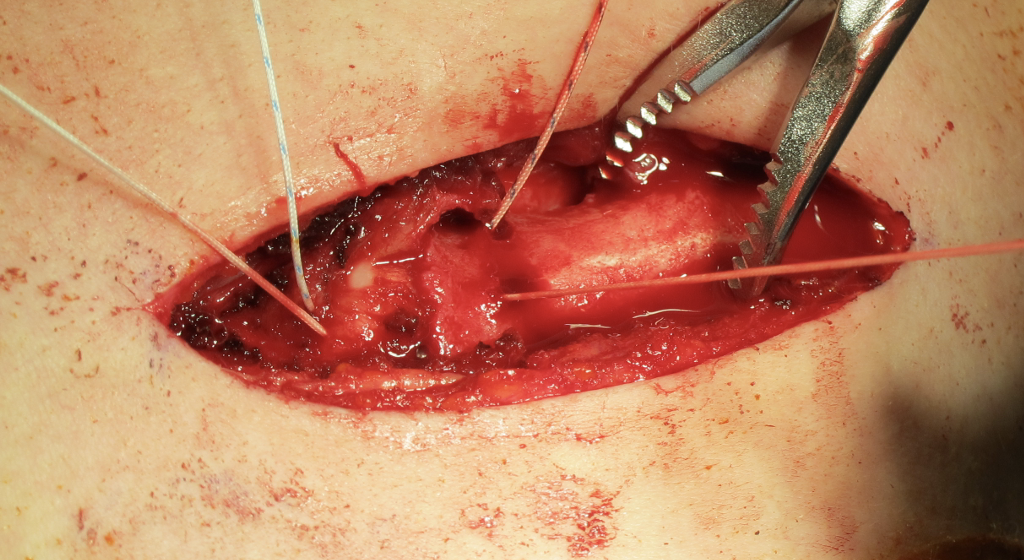

Open reduction of acute posterior sternoclavicular joint dislocation

Drill holes in manubrium and medial clavicle

Figure of 8 suture fixation